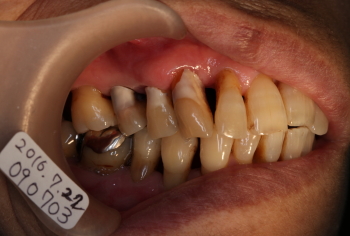

| 2016年07月22日 14番の歯牙の動揺と排膿と痛みとしみ |

| 2016年09月20日 FOP(歯肉剥離掻爬術)の約2カ月後の状態。 同部を外科処置した翌日から痛みも、出血、排膿、腫脹、しみもなくなり予後良好。 ただし、歯間部分(14、15番間)の退縮が認められる。 |